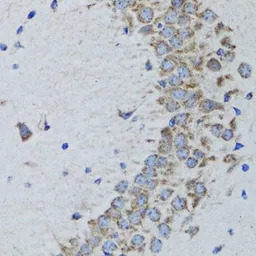

IHC-P analysis of mouse brain tissue using GTX55767 PTP1B antibody.

Dilution : 1:100